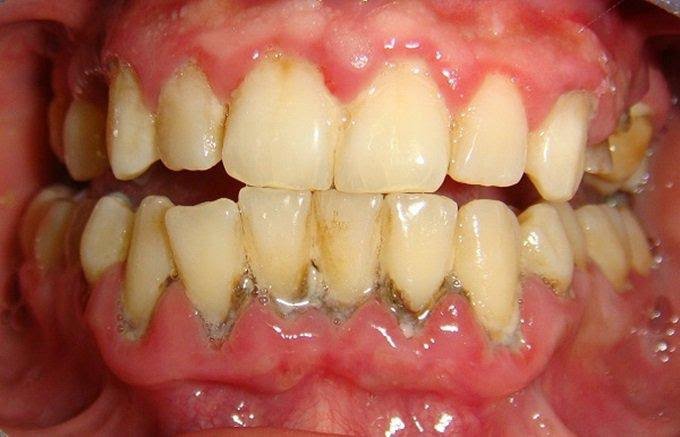

- Hạn chế nguy cơ mắc các bệnh lý răng miệng: cao răng là nơi trú ngụ của rất nhiều vi khuẩn có hại – chúng chính là nguyên nhân hàng đầu gây ra các bệnh lý như sâu răng, tụt lợi, viêm nha chu, mòn men răng,…

- Bảo vệ răng và xương hàm khỏe mạnh: vi khuẩn tích tụ trong cao răng theo thời gian sẽ xâm nhập vào sâu bên trong gây hư hỏng nướu và các tổ chức răng từ đó dẫn đến tiêu xương hàm và khiến răng bị lung lay, nguy hiểm hơn sẽ gây ra tình trạng mất răng hàng loạt.

- Loại bỏ hơi thở có mùi hôi hiệu quả: cao răng tích tụ quá dày sẽ khiến quá trình vệ sinh răng miệng trở nên khó khăn hơn. Vi khuẩn tích tụ nhiều sẽ gây ra mùi hôi khó chịu ở khoang miệng. Vì thế, để giữ được hơi thở luôn thơm tho, hãy loại bỏ các mảng bám cao răng.

- Phòng ngừa các bệnh liên quan: có thể bạn chưa biết nhưng vi khuẩn trong cao răng có thể là nguyên nhân gây nên các bệnh về tim mạch, viêm amidan, viêm họng,…